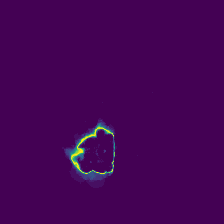

Diffusion models have shown impressive performance for generative modelling of images. In this paper, we present a novel semantic segmentation method based on diffusion models. By modifying the training and sampling scheme, we show that diffusion models can perform lesion segmentation of medical images. To generate an image specific segmentation, we train the model on the ground truth segmentation, and use the image as a prior during training and in every step during the sampling process. With the given stochastic sampling process, we can generate a distribution of segmentation masks. This property allows us to compute pixel-wise uncertainty maps of the segmentation, and allows an implicit ensemble of segmentations that increases the segmentation performance. We evaluate our method on the BRATS2020 dataset for brain tumor segmentation. Compared to state-of-the-art segmentation models, our approach yields good segmentation results and, additionally, detailed uncertainty maps.